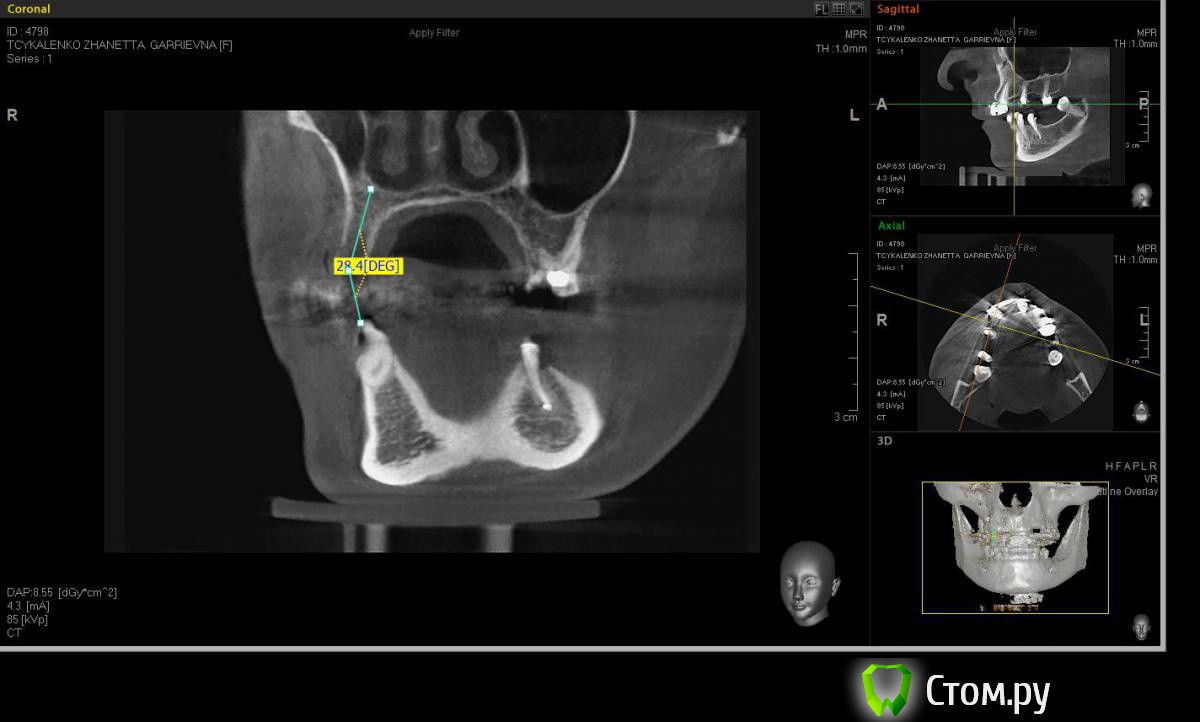

Евгений Ходыкин Опубликовано 20 мая, 2014 Поделиться Опубликовано 20 мая, 2014 Коллеги, прошу помощи в определении варианта аугментации в области 1.4 для адекватной в протетическом плане постановки имплантата. Адекватно ли здесь будет расщепление гребня при той оси импланта, которую я схематично выставил? Всем заранее спасибо) Ссылка на комментарий

Евгений Ходыкин Опубликовано 20 мая, 2014 Автор Поделиться Опубликовано 20 мая, 2014 Замерил... Ссылка на комментарий

АнтонТЛТ Опубликовано 20 мая, 2014 Поделиться Опубликовано 20 мая, 2014 Суть в том, что изначально не правильно угол замерили 1 Ссылка на комментарий

Евгений Ходыкин Опубликовано 20 мая, 2014 Автор Поделиться Опубликовано 20 мая, 2014 Суть в том, что изначально не правильно угол замерилиДак изначально я замерил строго по гребню, в условиях наибольшей ширины гребня, там угол под 30 и выходил. При ангуляции как у 1.5 у меня и получается дефицит кости, что примерно изобразил на схеме постановки имплантата. Поправьте, если не прав... Ссылка на комментарий